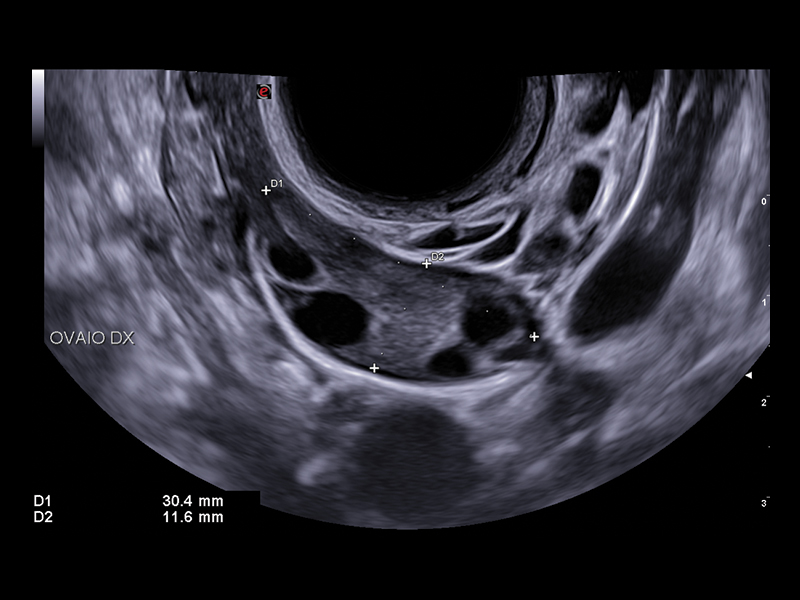

Esaote’s selection of probes for gynaecology provides high-quality images with outstanding contrast resolution, thus increasing clinical confidence in detecting abnormalities and pathologies in the female reproductive system, in both the transabdominal and transvaginal approaches.

The latest micro-convex end-fire transducer, E 3-12, has been designed by the Esaote Probe Centre of Excellence in Florence, with a short convergence radius for maximum resolution, and high capabilities of penetration while preserving the comfort your patient deserves.

The improved vascular image quality together with the extreme sensitivity of Esaote Doppler technologies (Power Doppler and microV) allow the detection of tiny vessels, to precisely assess the extent of the vascularization, to provide you with a better understanding of certain pelvic abnormalities such as fibroids, polyps, or endometriosis conditions.